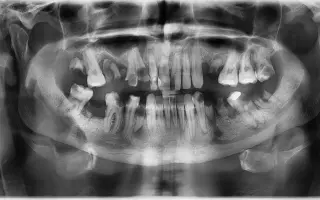

Kvôli tejto poruche sa môj zdravotný stav dostal až k vysokým zápalovým ochoreniam a rozpadu zubov.. konkretne  Chronická osteomyelitída sánky. Tieto zápaly sprevádzané neskutočnými bolesťami mi bránia v bežnom živote, nájsť si prácu a neustále užívanie liekov proti bolesti už začína byť aj rizikové pre vnútorné orgány.

A tak som nabral odvahu a túžbu sa po 20 rokoch usmiať. Išiel som na konzultáciu, kde mi nastavili plán liečby, a to extrakciu 11 zubov vyčistenie  odumretého  tkaniva z kosti  a opravy všetkých ostatných – úplnú rekonštrukciu. Keďže táto liečba je veľmi nákladná a vyžaduje rýchly zákrok, v úplnej  narkoze,pretože môj stav je akútny, prosím o pomoc na zlepšenie môjho života. Túžim začleniť sa do spoločnosti a usmievať sa, žiť bez bolesti a schuti sa najesť.

Peniaze budú použité na potrebné vytrhanie a rekonštrukciu zubov, liečbu ďasien a kostí, ktoré sú napadnuté zápalom a na zubnú náhradu, aby sa zuby v ústach a v kosti nezačali posúvať po vytrhnutí. Zubár nastavil približnú cenu na 4 500 €, ako najlacnejší variant.